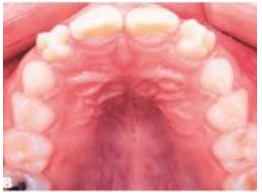

Observe a imagem, abaixo:

Ao analisarmos a imagem, o que se observa, que

justifique a maloclusão, é a presença de cúspide em: